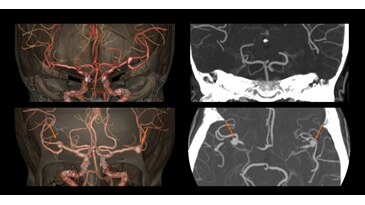

Brain with contrast at 1 mSv1